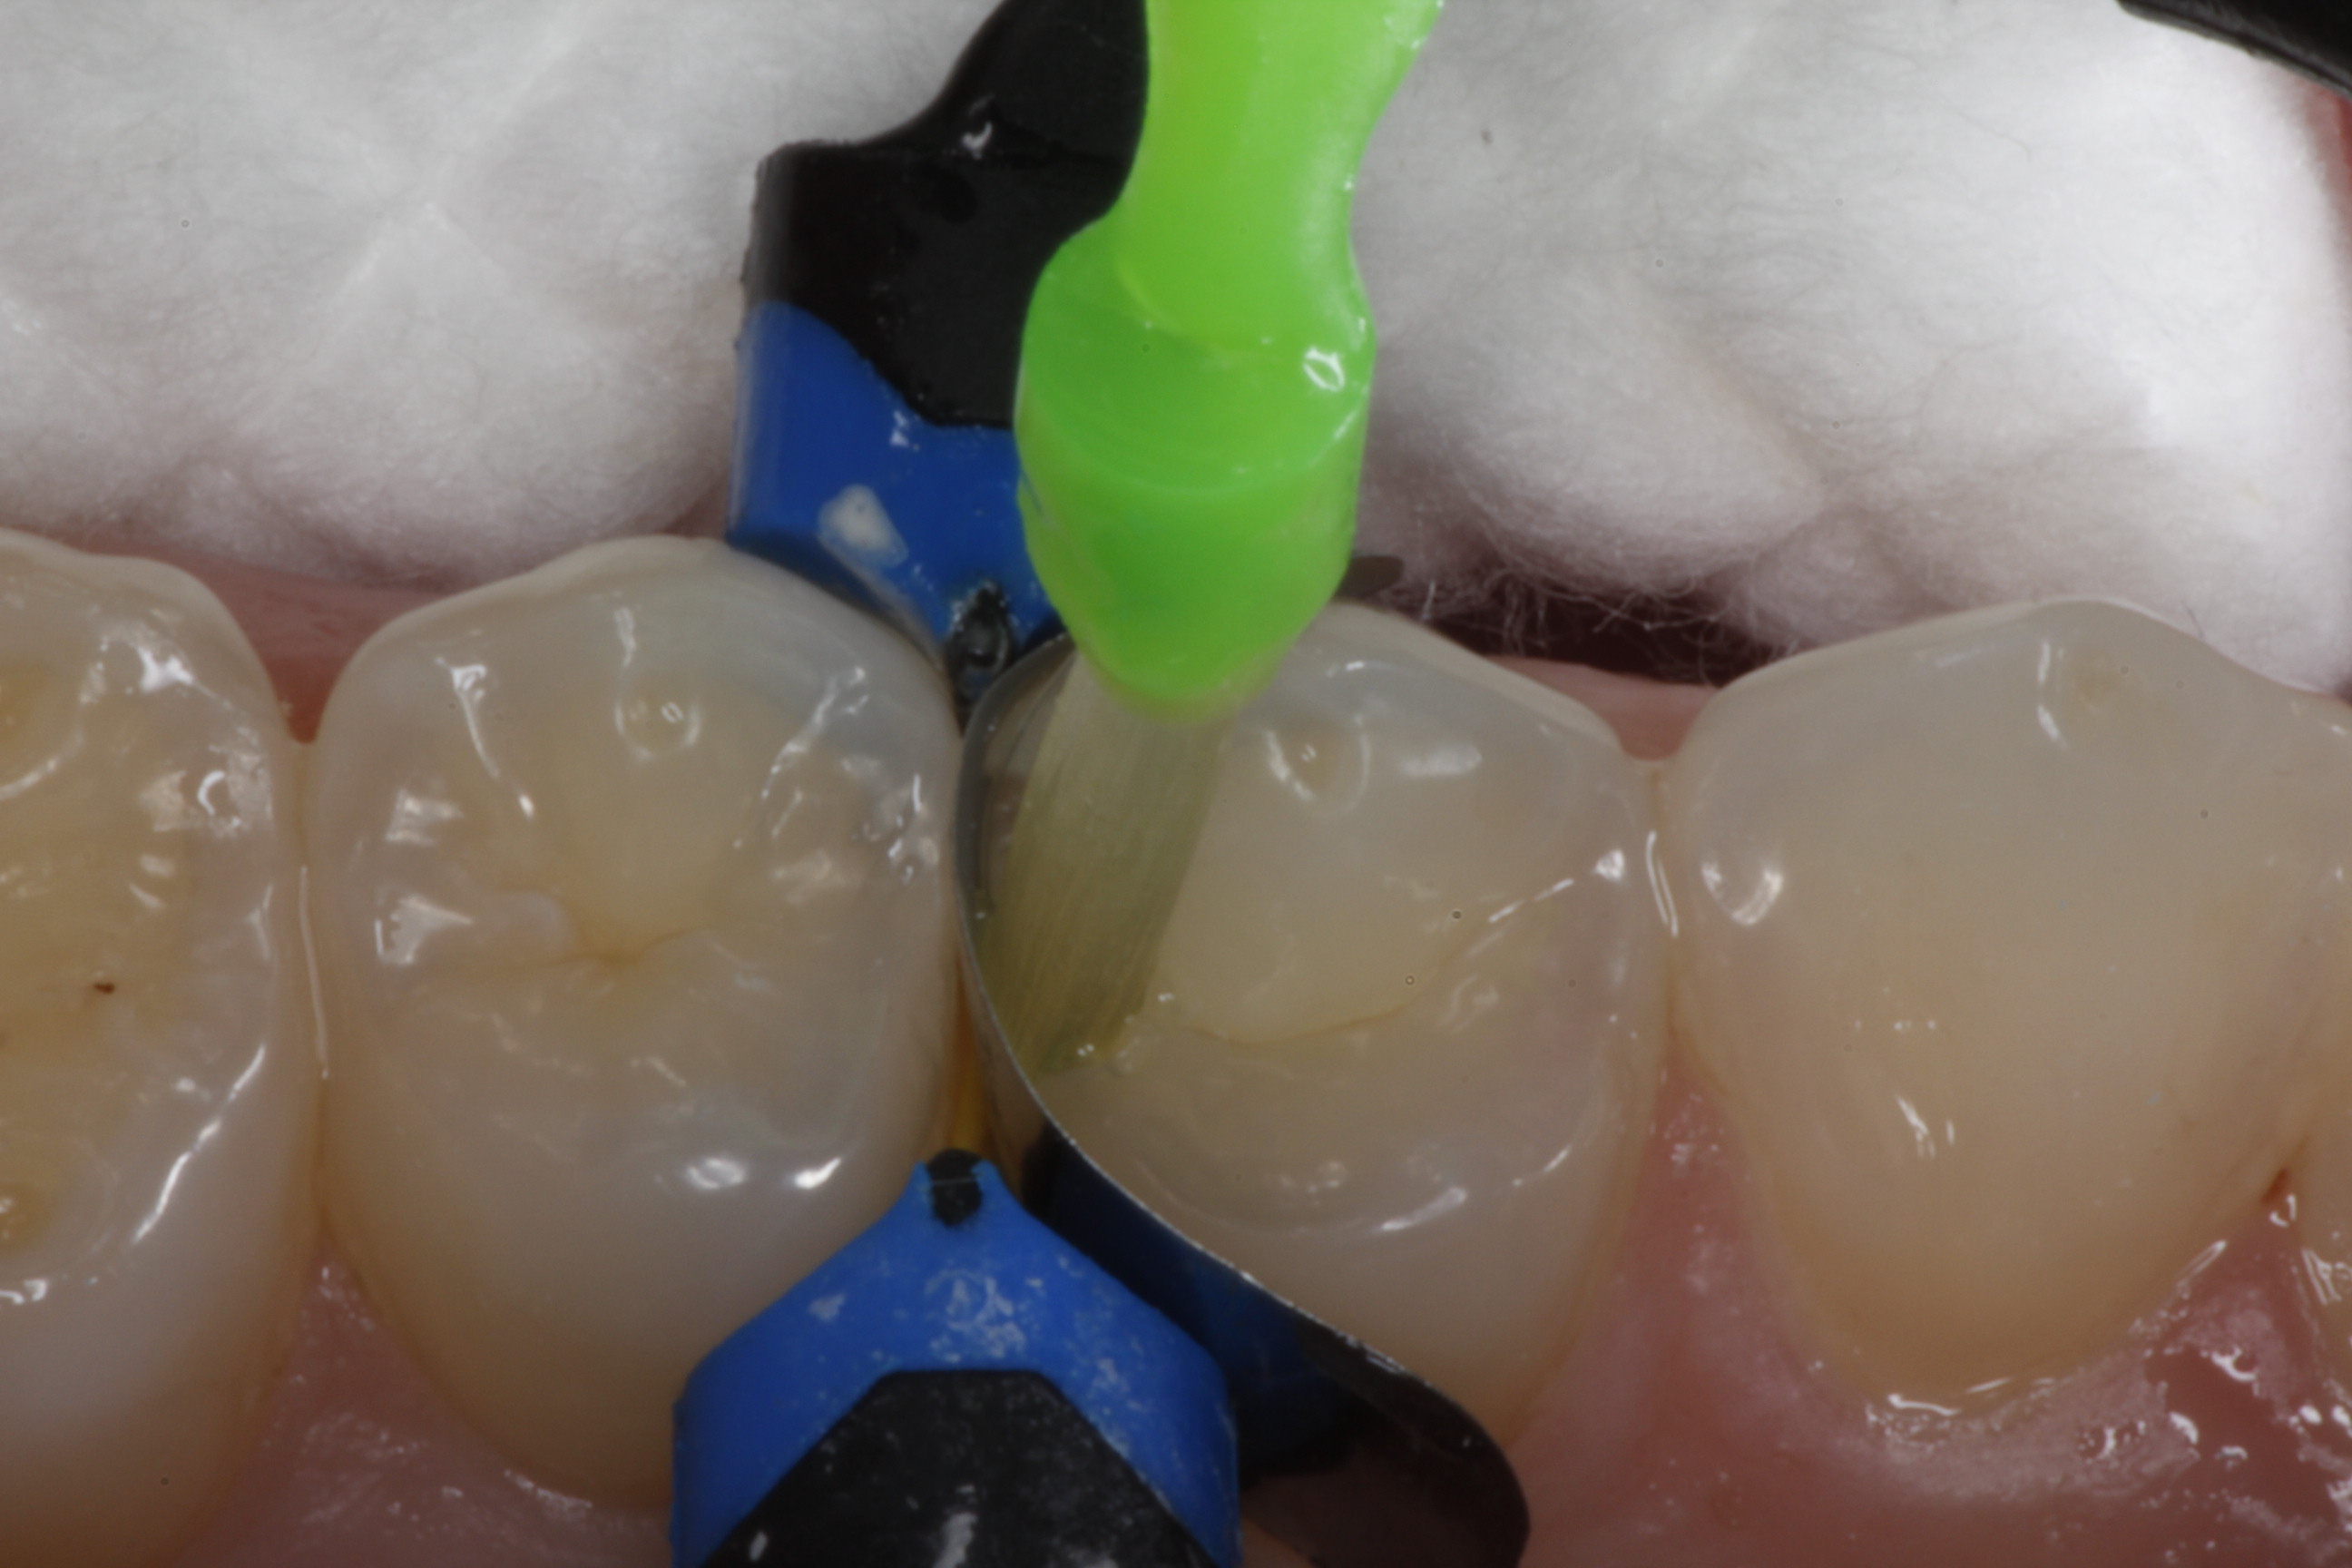

Fig 10. A Giomer bulk-fill flowable is used for this conservative slot preparation so that the entire cavity can be filled with one increment even though the depth of the proximal box is approximately 4 mm.

Figure 10